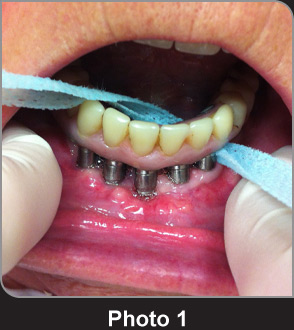

寬牙線X-Ribbon?用于清潔種植齒橋的案例。 寬大的粗紗布條圍繞牙齒和齒橋表面進行清潔極其有效。

寬牙線X-Ribbon?用于清潔齒橋,粗紋理的材料可以“抓住”斑塊和牙垢進行徹底清潔。